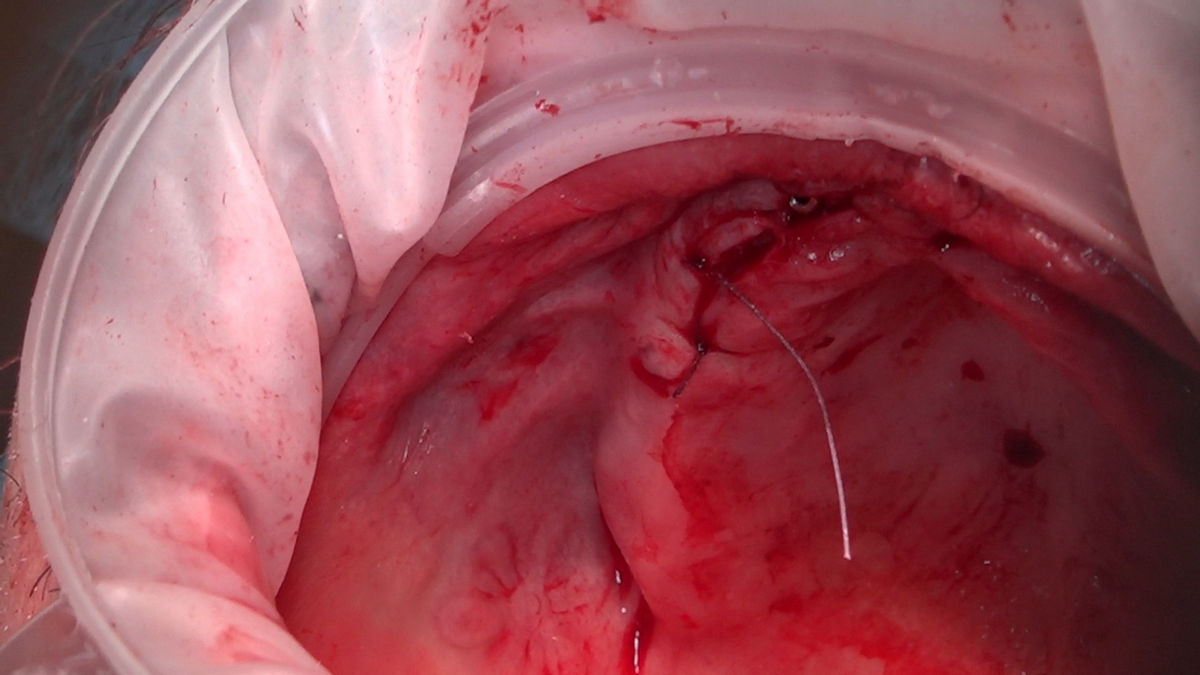

Chirurgia implantologiczna to temat wiodący 5 Sesji X Sezonu Practiculum Implantologii, która się odbyła 23-24 października 2020 roku. Bierze w nim udział 16 adeptów implantologii stomatologicznej. Zabiegi z udziałem Pacjentów jak zwykle poprzedziło omówienie i planowanie, tym bardziej, że zgodnie z planem wykonana została implantacja z wykorzystaniem szablonu chirurgicznego, który przygotowało laboratorium dentystyczne Wiligała Lab. Kursanci wykonywali szereg zabiegów implantologicznych i chirurgicznych oraz regeneracyjnych z zastosowaniem PRF, w tym sinus lift. Przeprowadzali je pod kierunkiem Lidera Umiejętności Implantologicznych dr n.med. Violetty Szycik, która wysoko oceniła wykonanie zabiegów.